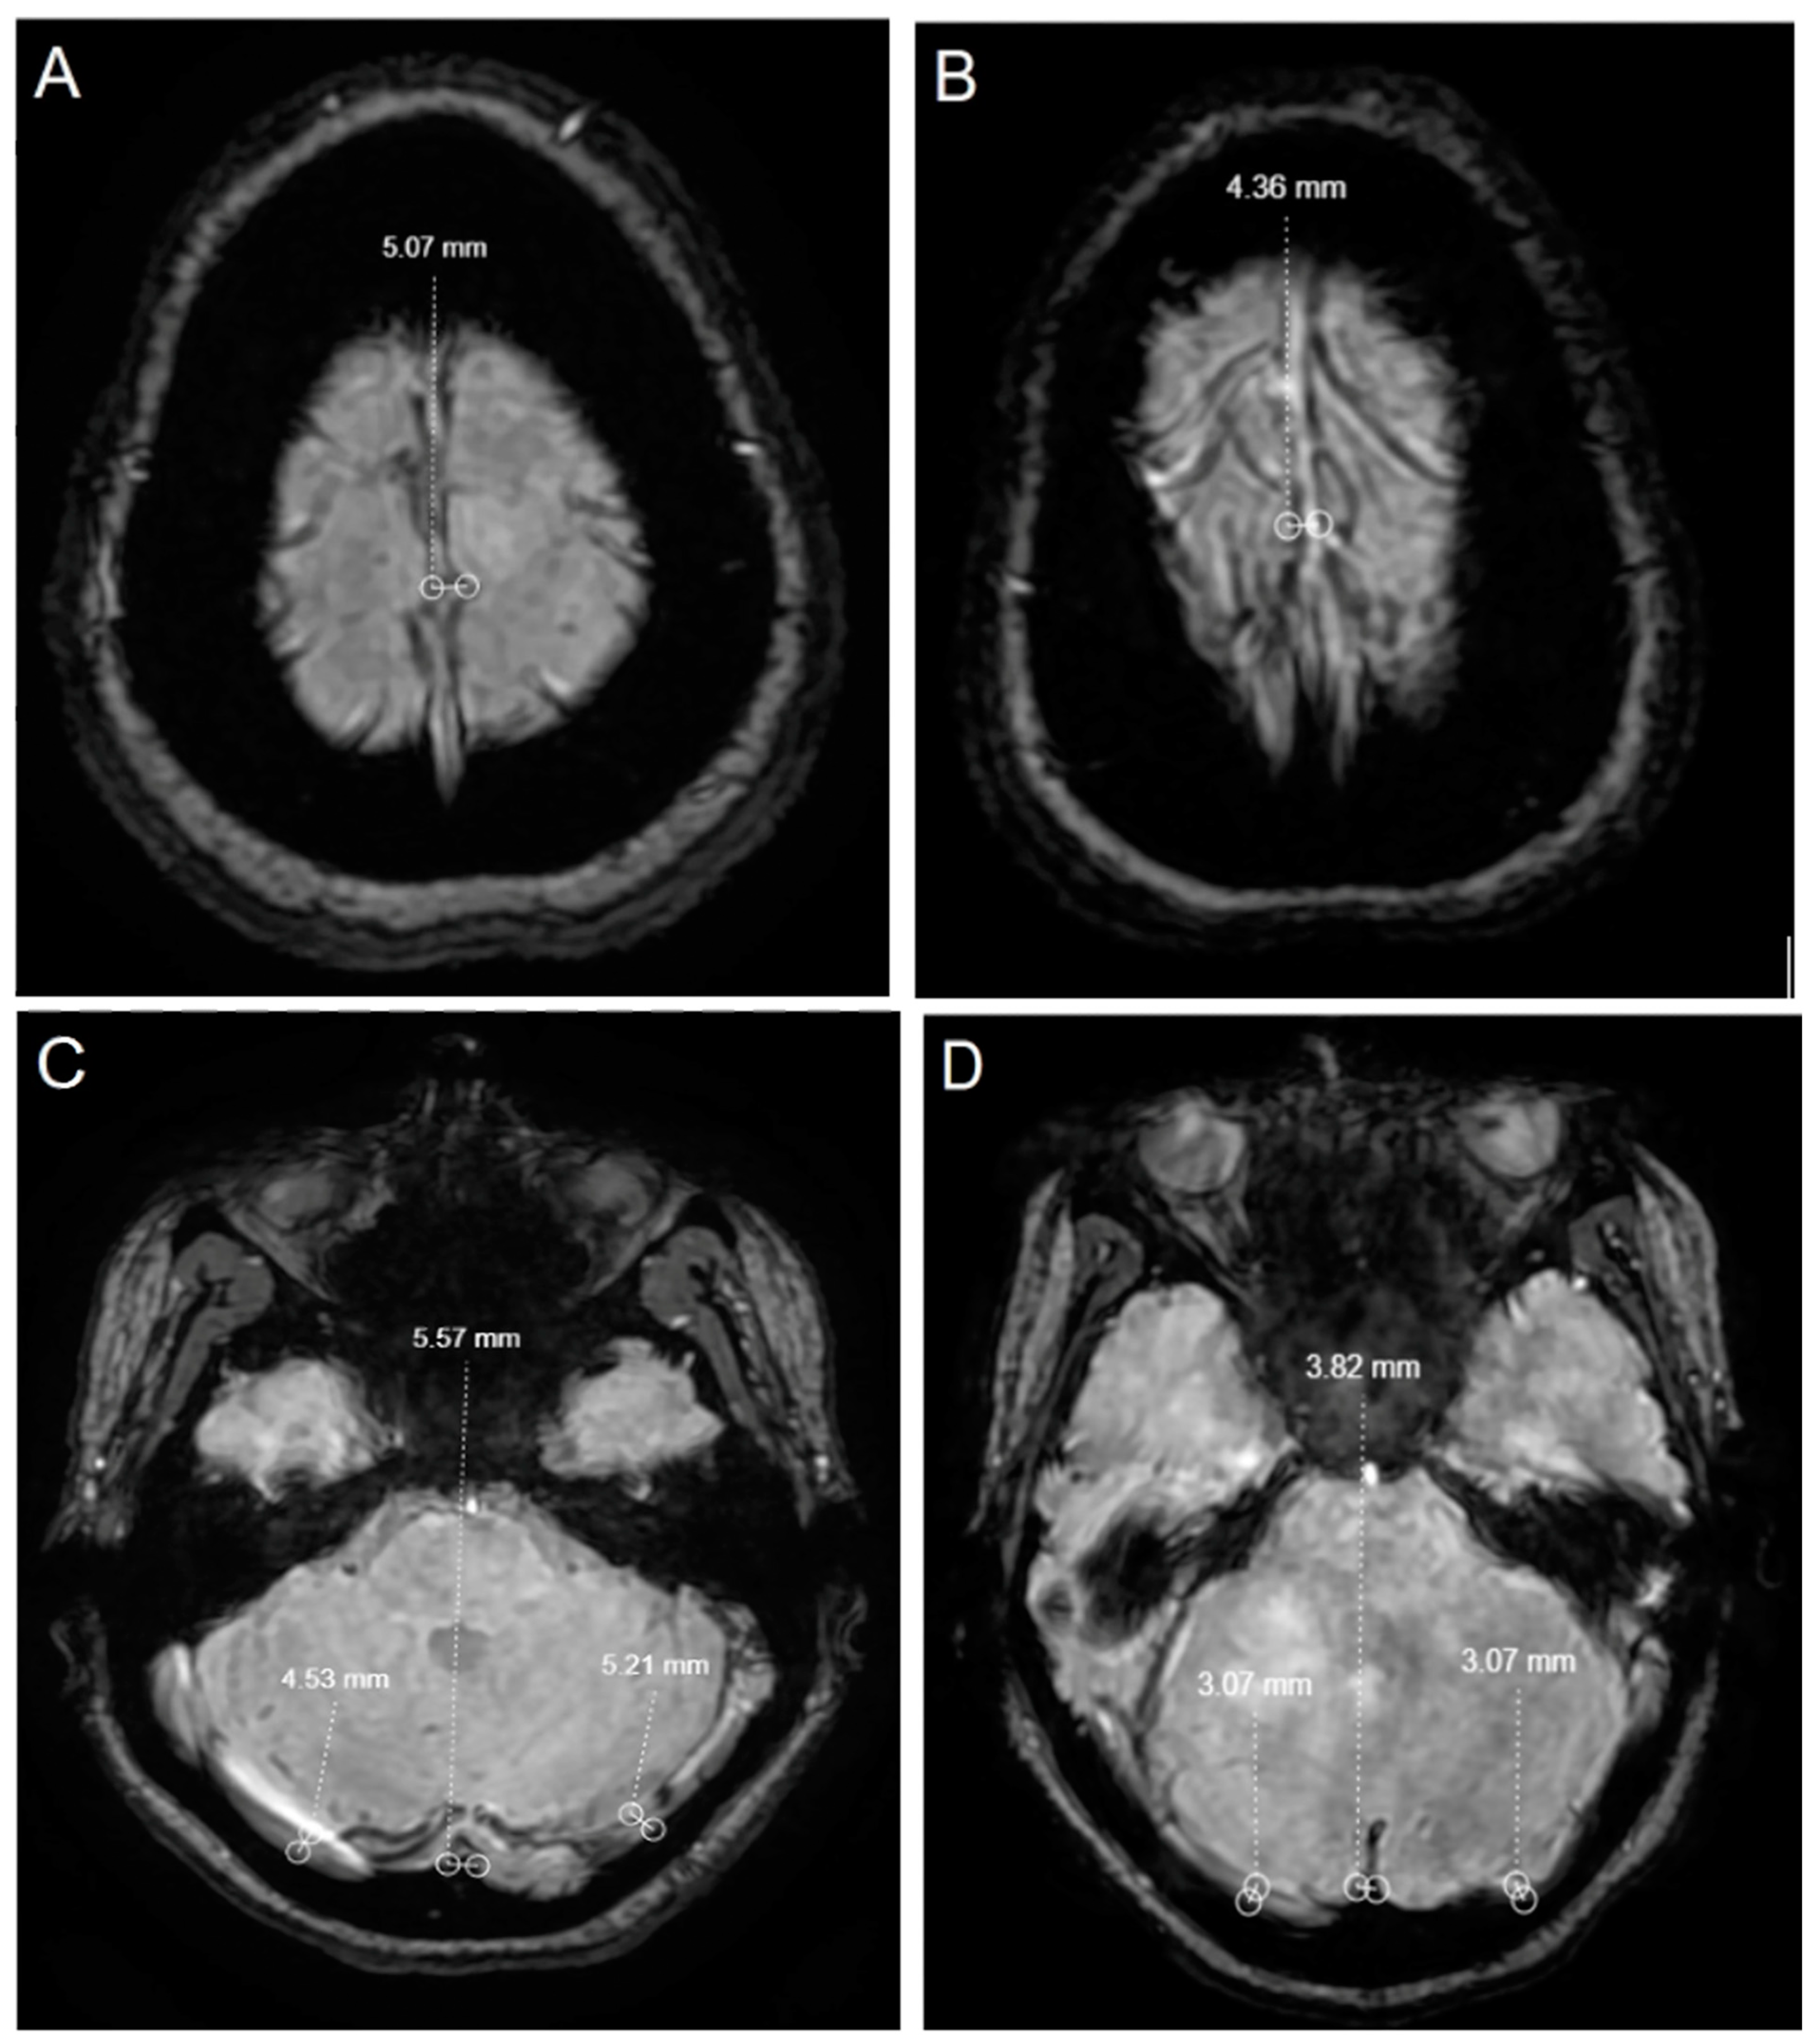

| SSS | 5.4 ± 0.9 | 4.8 ± 0.6 | 5.9 ± 0.8 | <0.001 | <0.001 |

| Sinus rectus | 4.6 ± 0.8 | 4 ± 0.7 | 5 ± 0.5 | <0.001 | <0.001 |

| Right transverse sinus | 5.2 ± 1.6 | 4.8 ± 1.4 | 5.5 ± 1.7 | 0.020 | 0.015 |

| Left transverse sinus | 4.1 ± 1.6 | 3.7 ± 1.4 | 4.4 ± 1.7 | 0.005 | 0.003 |